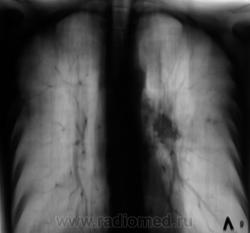

1 срез в боковой проекции.

Приложения:

Следующий срез.

Доделали один срез - 5 см. в прямой проекции.